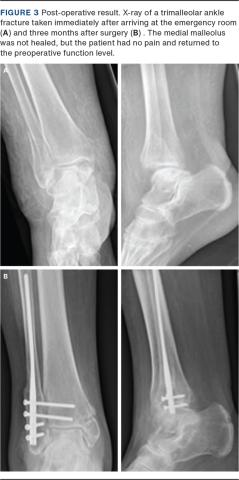

A total of 32 patients were included in this analysis with a mean follow-up period of 8.3 months (range: 3-46 months). Fracture healing (Figure 3) was observed in 93.7% of the lateral malleolus and in 50% of the medial malleolus at the last radiographic follow-up.

Billede